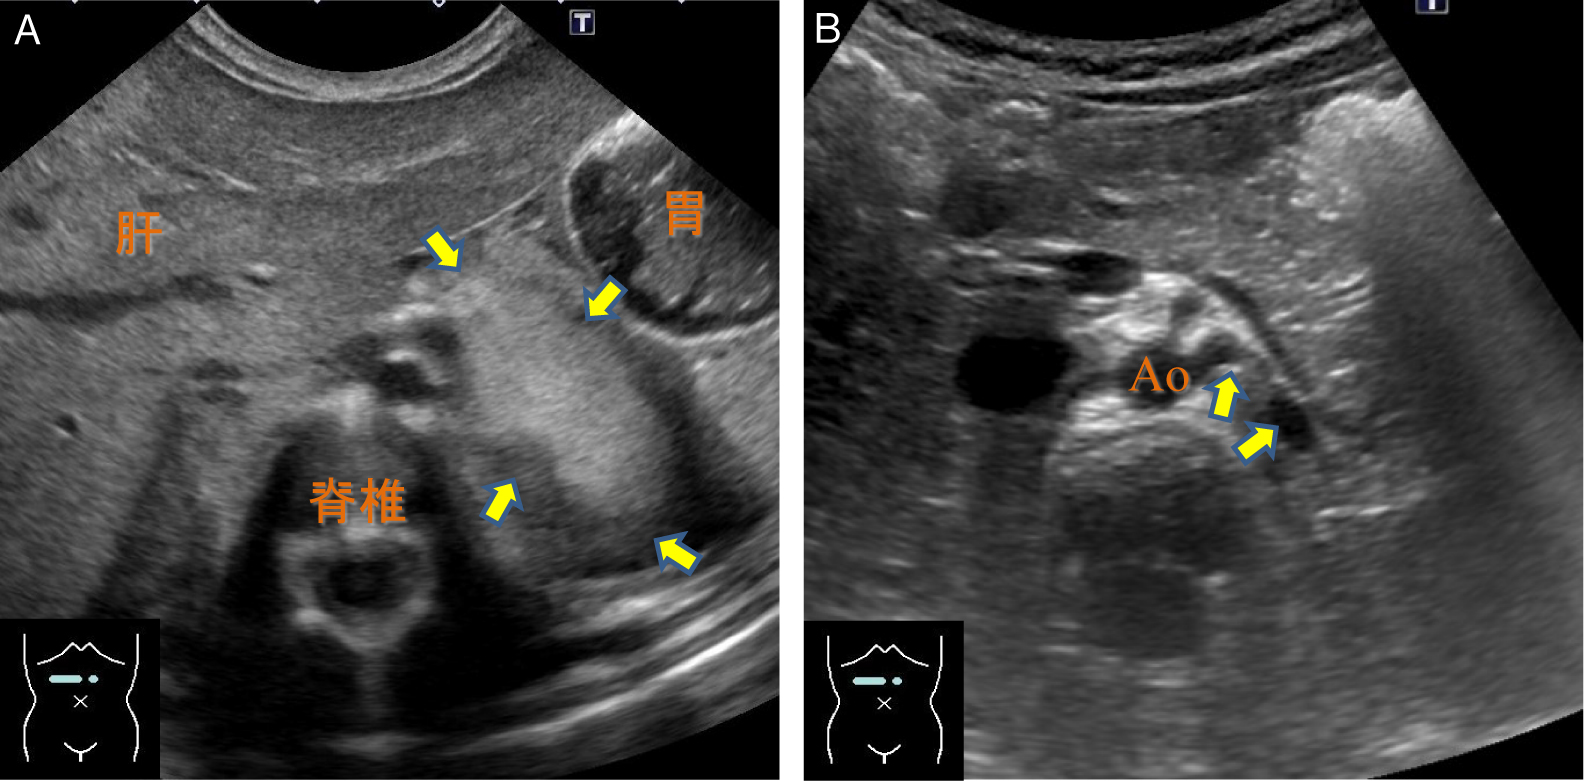

5. 肺腫瘍肺腫瘍は胸膜に接している場合には超音波で描出可能である(Fig.16).小児では成人型肺癌はまれで,胸膜肺芽腫の占める割合が高いため22),肺腫瘍を疑う場合には超音波検査を積極的に施行すると有用である.胸壁に発生する神経芽腫やEwing肉腫ファミリー腫瘍とは,壁側胸膜やlung slidingの位置から鑑別可能である(Fig.17).

胸壁・胸膜に接して巨大な充実性腫瘍が認められる(→).内部に血流を伴い,胸膜とは明確な弁別が困難であり,胸膜肺芽腫が疑われる所見である.

胸壁腫瘍と肺腫瘍との鑑別には,壁側胸膜の位置が参考になる.胸壁由来の神経芽腫では,胸壁と腫瘍との間には胸膜が介在せず,腫瘍と肺との間に介在している(*).Lung slidingはこの部位で描出される.

肺分画症は中枢気管支との直接交通はなく,側副路による交通が確立されなければ含気のない肺区域として描出される.大循環(主として腹部大動脈)から動脈血流を供給されることが特徴であり,超音波で異常血管を直接描出することが可能である(Fig.19).

A:中枢気管支との直接交通を欠き,側含気のない肺区域として描出される(→).腹部大動脈から直接分岐する異常血管が描出されている(→).